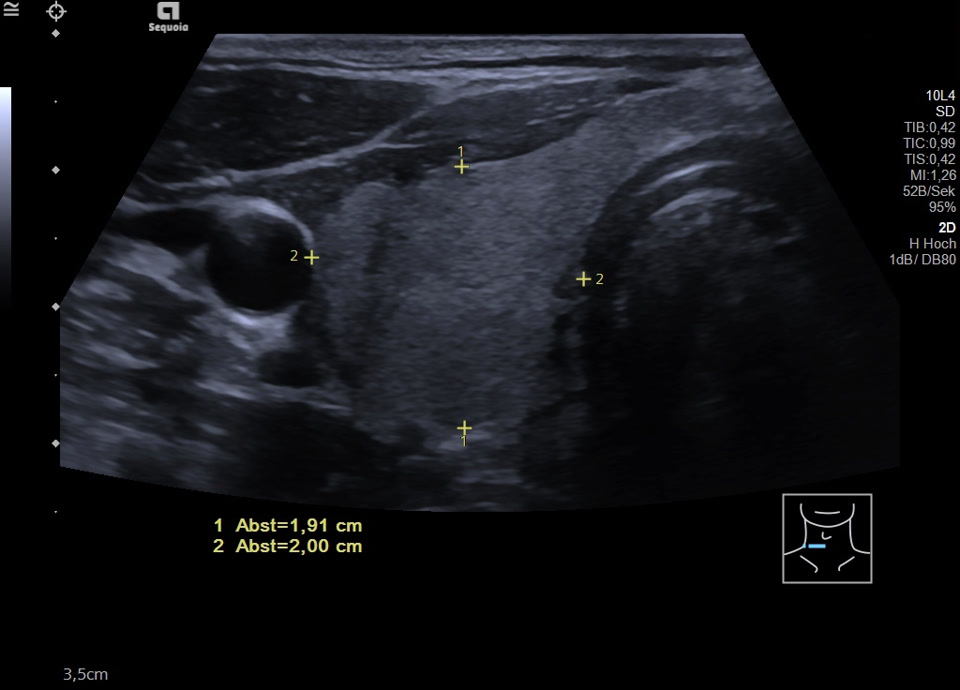

45-year-old male presented patient with persistent sore throat and general symptoms following an EBV-infection. An external diagnosis of post-infectious de Quervain’s thyroiditis had already been made, and a two-week course of corticosteroid therapy was administered. Initial clinical improvement with reduced throat pain was noted under treatment, but symptoms reoccurred after discontinuation of corticosteroids. Laboratory findings revealed leukocytosis of 12,000/µl and CRP of 113 mg/l. Sonographically, a bilaterally enlarged thyroid gland with diffusely hypoechoic areas and inhomogeneous parenchyma was observed. Combined with the patient history, this was characteristic of a subacute thyroiditis with relapse after short-term corticosteroid therapy. Prolonged corticosteroid therapy with slow tapering was performed. Under this regimen, marked clinical improvement occurred within weeks; follow-up ultrasound four months later showed a normal-sized thyroid with only mildly inhomogeneous parenchyma, consistent with resolving thyroiditis.